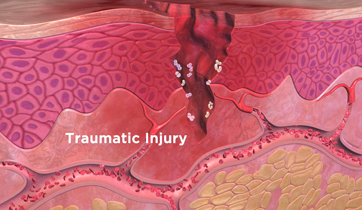

Cervical Facet Syndrome and Rhizotomy

Courtroom Animation for Law firm

This animation was created to be used as demonstrative evidence in a personal injury case. Visual aids such as this can help the jury understand complex medical injuries and procedures. We can customize each animation to be case specific.